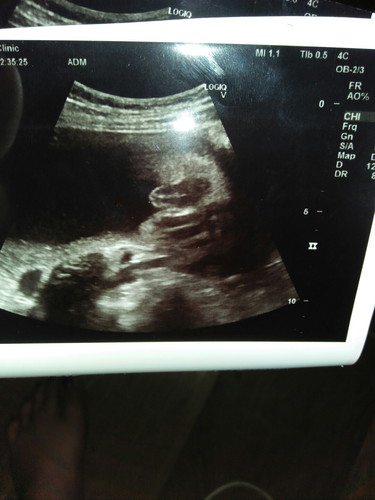

เพศลูก

แม่ๆช่วยดูหน่อยจ้า ญ หรือ ช

น่าจะญนะของเราก็กรีบๆเเบบนี้

ลูกสาวค่ะแม่ มาเป็นกลีบเลย

น่าจะ ญ นะคะ

น่าจะหญิงจ้า

ญ